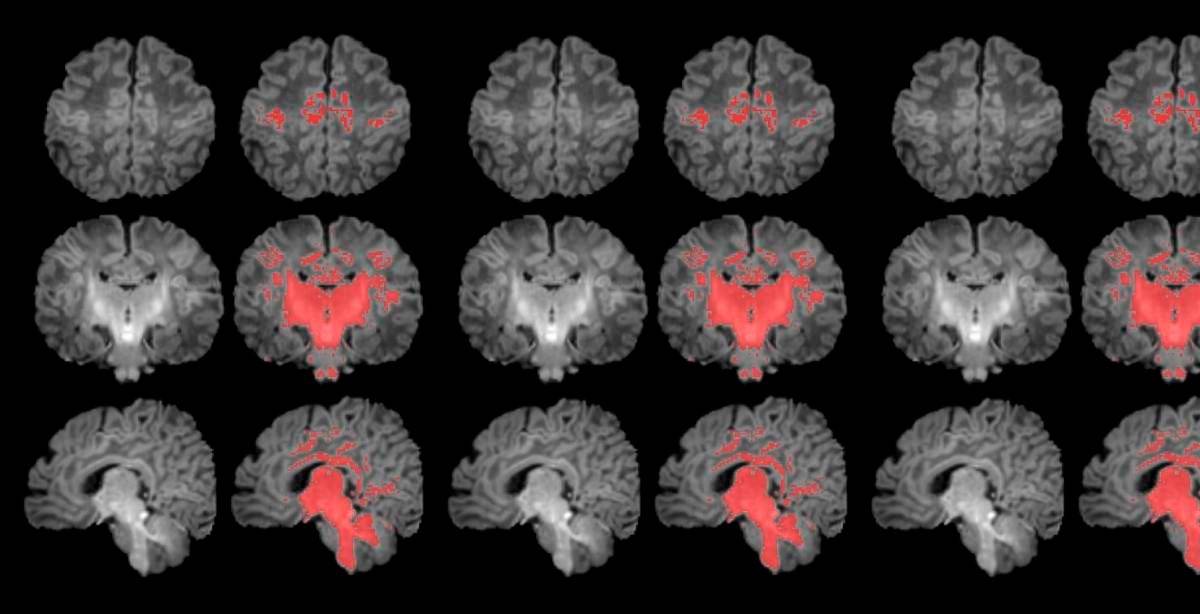

• Es el primer estudio que mide con resonancia magnética la mielinización cerebral de los recién nacidos. FOTO Pujol et al., 2025 | ISGlobal

Es el primer estudio que mide con resonancia magnética la mielinización cerebral de los recién nacidos. FOTO Pujol et al., 2025 | ISGlobal

La mielinización es un proceso clave en la maduración del cerebro, en que la mielina recubre las conexiones neuronales y las hace eficientes para la transmisión de información. Los recién nacidos de madres expuestas a niveles más altos de partículas finas en suspensión durante el embarazo muestran una mielinización más lenta en esta etapa tan precoz de la vida.

En este sentido, según explica Gerard Martínez-Vilavella, investigador de la Unidad de Resonancia Magnética del Servicio de Radiología del Hospital del Mar, integrado en la red dibi, y del Instituto de Investigación del Hospital del Mar, “en el estudio vemos que el proceso de mielinización, un indicador de maduración cerebral que avanza progresivamente con el tiempo, presenta un ritmo más lento en los recién nacidos más expuestos a PM2.5 durante el embarazo”.

Los resultados muestran una correlación clara entre una mayor exposición materna a PM2.5 durante el embarazo y una menor mielinización en el cerebro de los recién nacidos.

“La contaminación atmosférica, concretamente las PM2.5, se asocia con una alteración en el proceso de mielinización, un mecanismo esencial de maduración cerebral. Por ello hay que continuar controlando la contaminación y estudiar cómo esta ralentización puede influir en el desarrollo posterior del cerebro de los niños y niñas”, expresa Martínez-Vilavella.